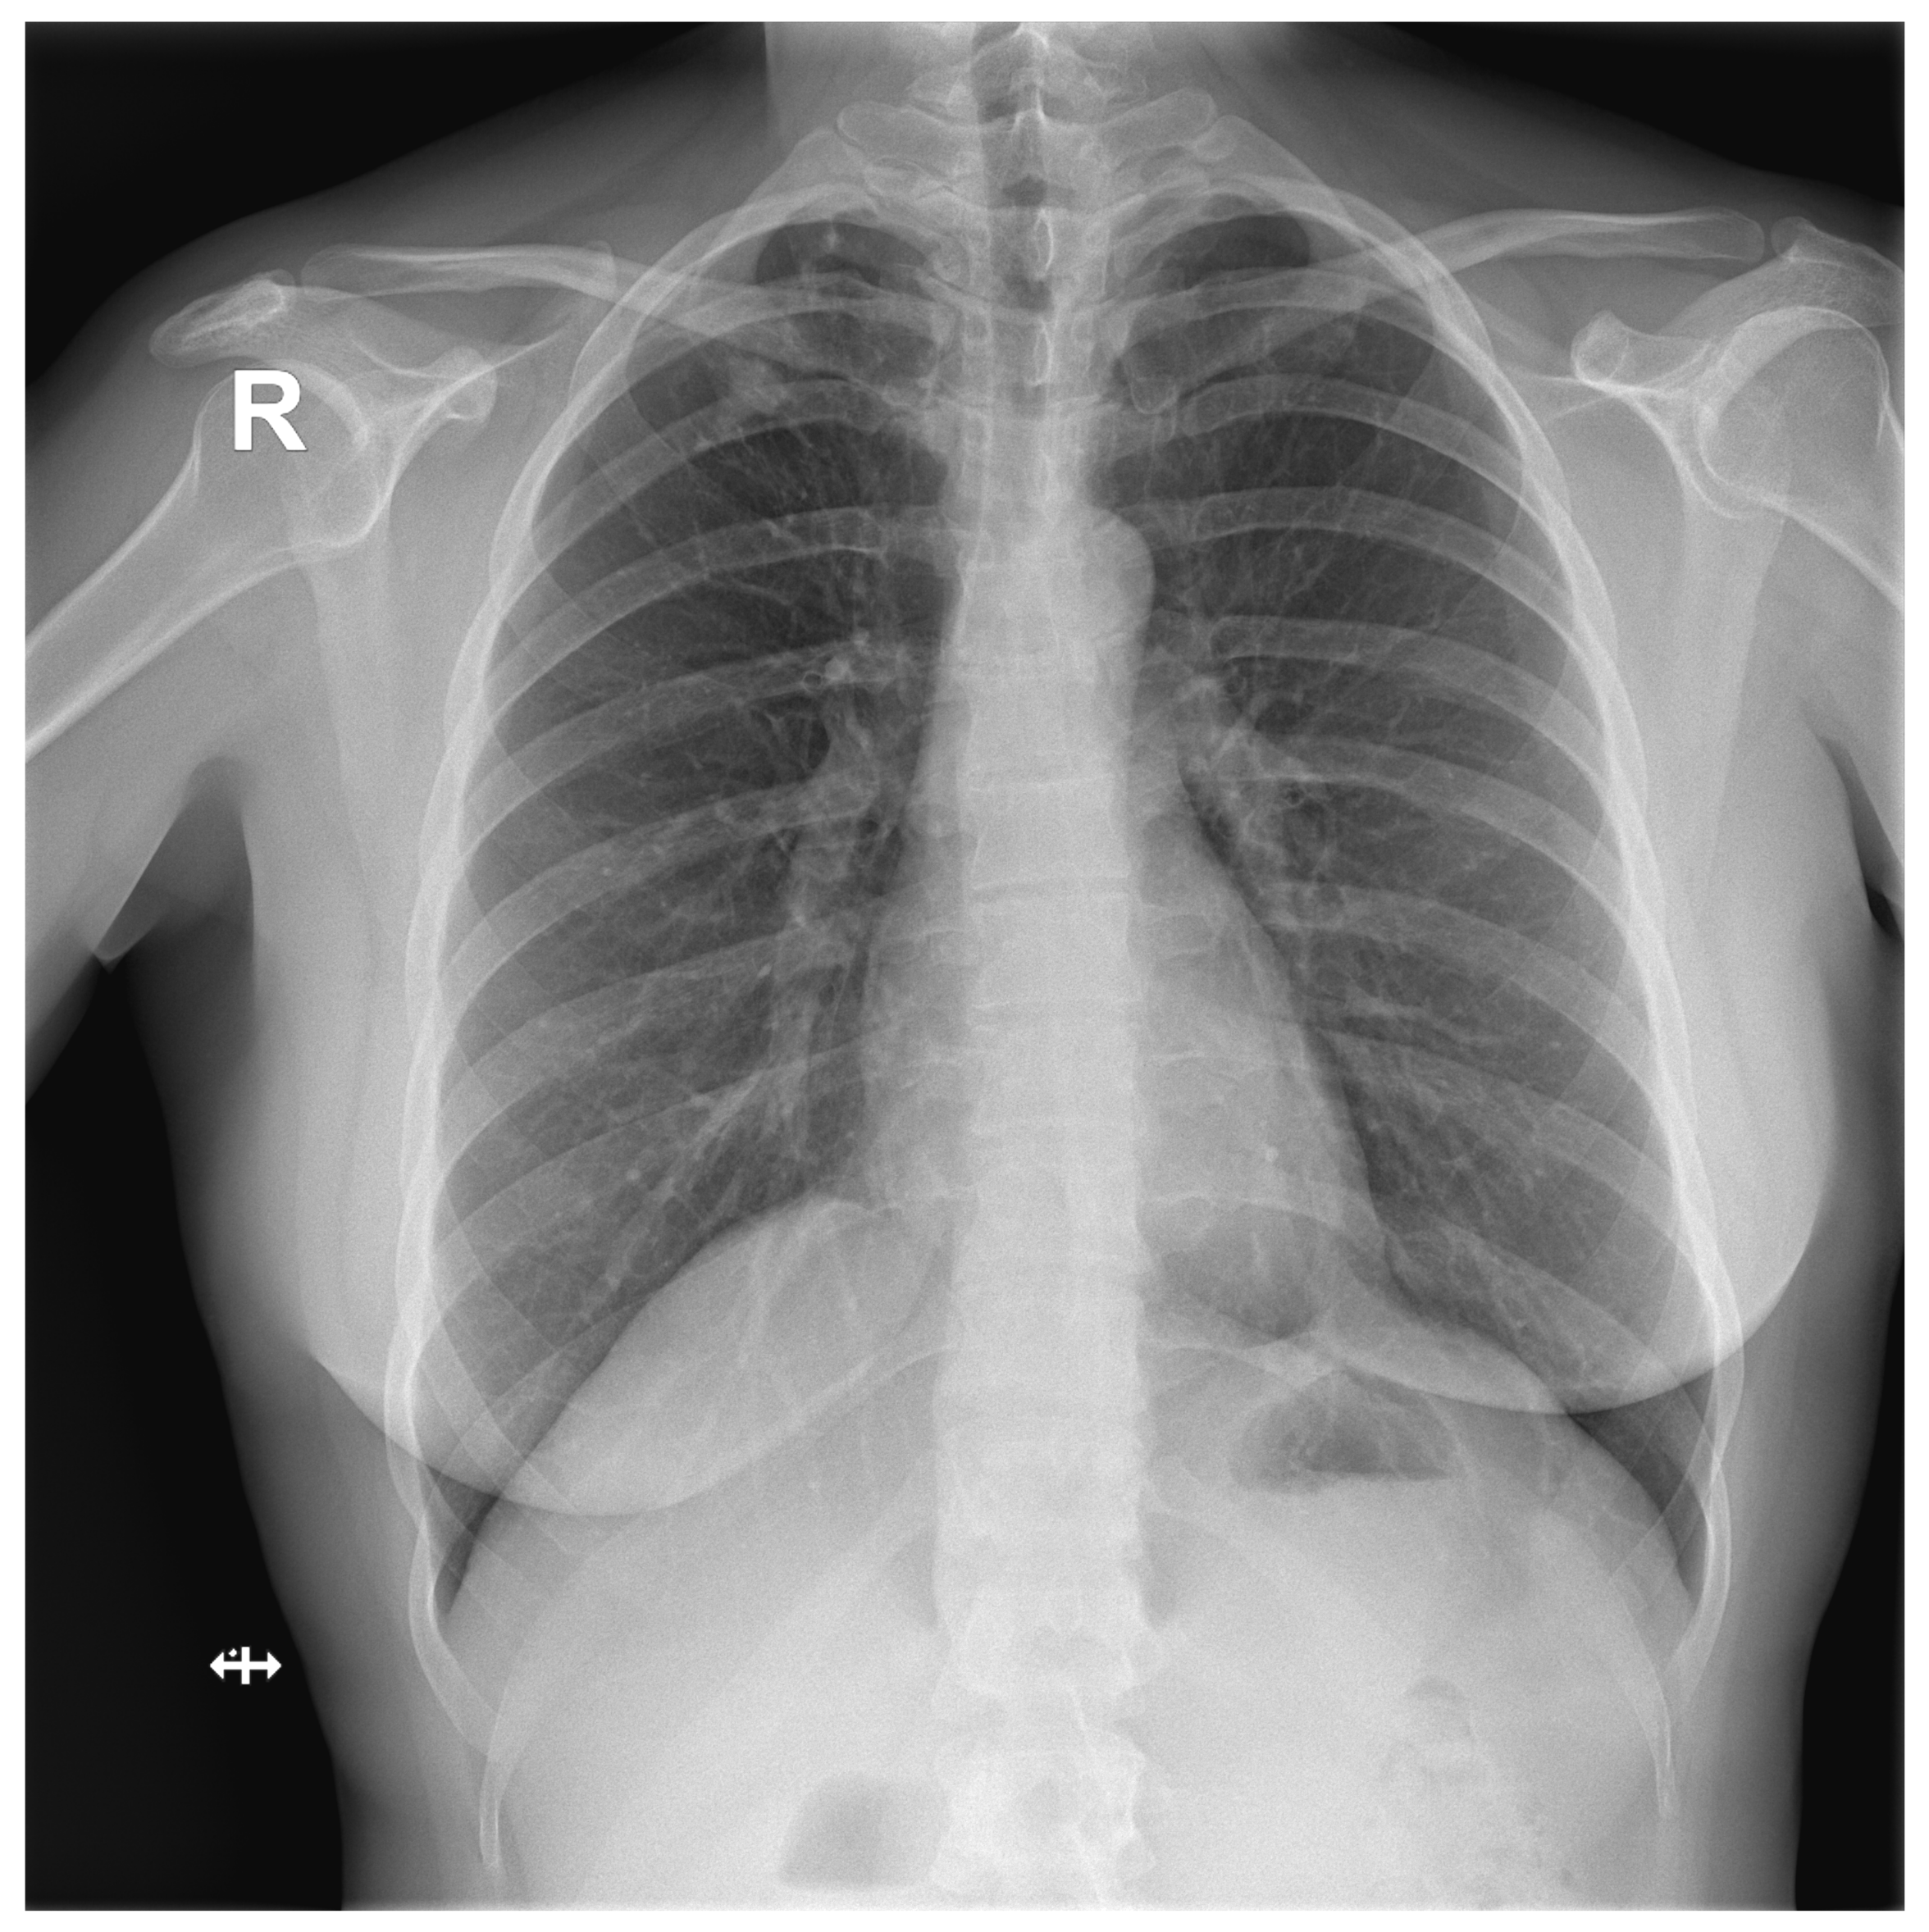

Figure A1.

False Negative image incorrectly classified by DLAD software during internal software validation. The software failed to detect a rib fracture.